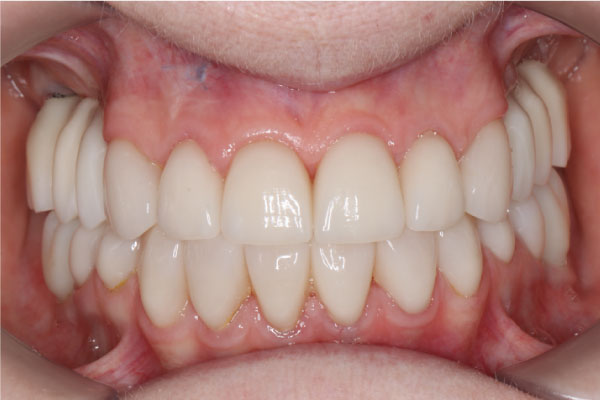

Имплантация зубов: фото «До» и «После»

All-on-4

All-on-6